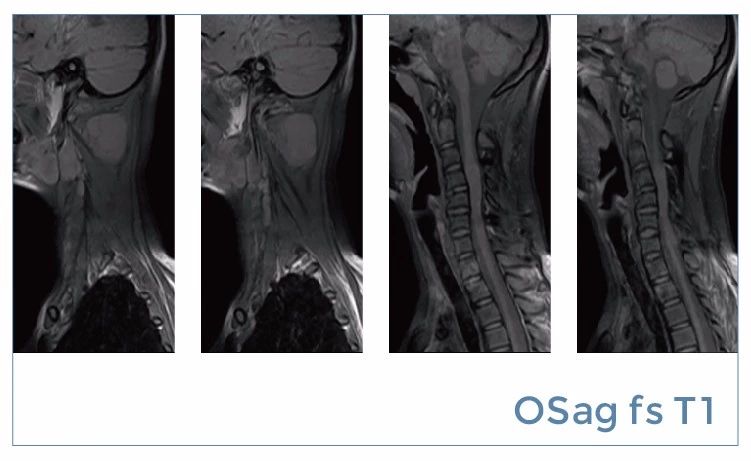

【朗润影像档案】20190816磁共振影像病例结果讨论